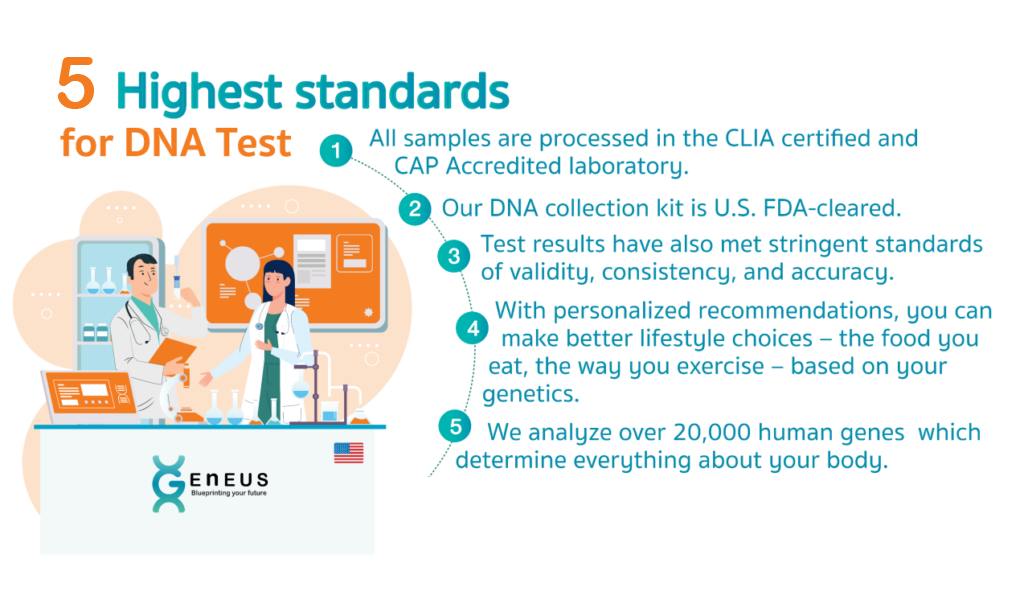

Our Cutting-edge Technology

Our laboratory provides highest quality data using cutting-edge systems and

technologies. You can be assured that your test results

are scientifically proven and accurate.